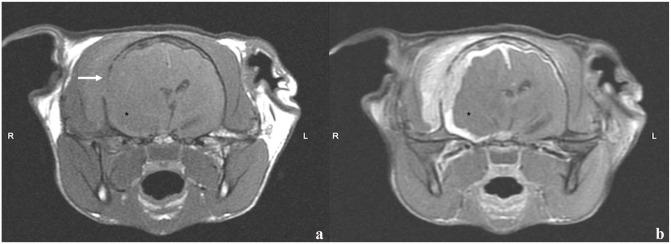

Case summary: A 4-year-old female neutered Scottish Fold shorthair cat was presented for further investigation of circling towards the right. MRI of the brain revealed an extensive, right-sided temporal muscle lesion with associated frontotemporal bone osteolysis, intracranial, extra-axial extension along the calvarial convexity with severe pachy- and leptomeningeal thickening and contrast enhancement, and an intra-axial space-occupying lesion in the right piriform lobe. The regional lymph nodes were moderately enlarged. Cytology of the right parotid lymph node and the temporal muscle was performed and histiocytic sarcoma (HS) was diagnosed. The owners elected euthanasia.

Relevance and novel information: HS of the central nervous system (CNS) is a very rare neoplastic condition in cats. Although a few case reports mention MRI, to our knowledge, the characterisation of MRI features of feline CNS HS have not been investigated in detail. Therefore, the aim of this case report was to describe the MRI characteristics in a feline HS involving not only the CNS, but also the fronto-temporal bone, temporal muscle and the regional lymph nodes. In particular, aggressive neoplastic bone invasion was a novel finding.